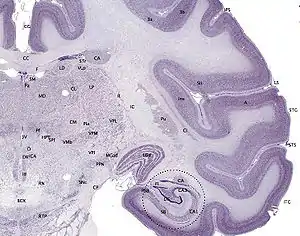

The hippocampus, including the dentate gyrus, has the shape of a curved tube, which has been compared to a seahorse, and to a horn of a ram, which after the ancient Egyptian god often portrayed as such takes the name cornu Ammonis. Its abbreviation CA is used in naming the hippocampal subfields CA1, CA2, CA3, and CA4.[20] It can be distinguished as an area where the cortex narrows into a single layer of densely packed pyramidal neurons, which curl into a tight U shape. One edge of the "U," – CA4, is embedded into the backward-facing, flexed dentate gyrus. The hippocampus is described as having an anterior and posterior part (in primates) or a ventral and dorsal part in other animals. Both parts are of similar composition but belong to different neural circuits.[22] In the rat, the two hippocampi resemble a pair of bananas, joined at the stems by the commissure of fornix (also called the hippocampal commissure). In primates, the part of the hippocampus at the bottom, near the base of the temporal lobe, is much broader than the part at the top. This means that in cross-section the hippocampus can show a number of different shapes, depending on the angle and location of the cut.

In a cross-section of the hippocampus, including the dentate gyrus, several layers will be shown. The dentate gyrus has three layers of cells (or four if the hilus is included). The layers are from the outer in – the molecular layer, the inner molecular layer, the granular layer, and the hilus. The CA3 in the hippocampus proper has the following cell layers known as strata: lacunosum-moleculare, radiatum, lucidum, pyramidal, and oriens. CA2 and CA1 also have these layers except the lucidum stratum.[23][24]